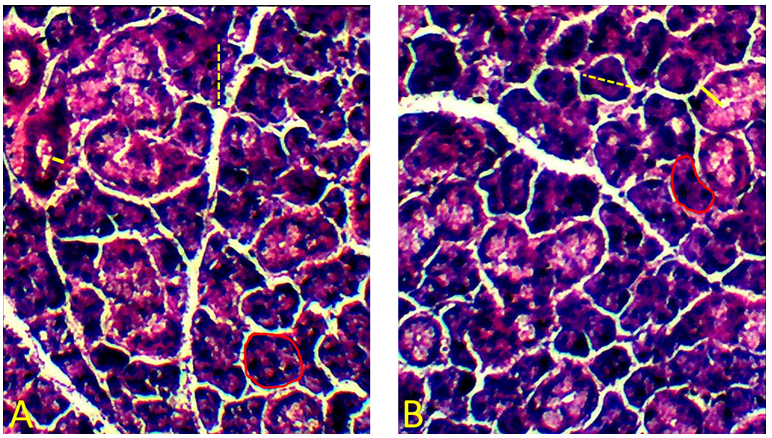

Table 1 shows the results of the morphometric analyses for the three major salivary glands. The parotid gland’s acinar diameters and ductal thicknesses were significantly smaller in the T group than in the C group (Figure 1). No further differences were found regarding the other morphometric parameters of parotid glands, nor for the morphometric parameters of sublingual (Figure 2) and submandibular glands (Figure 3).

Figures 1, 2, and 3 present photomicrographs of the parotid, submandibular, and sublingual salivary glands, respectively.

Benzodiazepine drugs induce xerostomia, which is the sensation of dry mouth (Tredwin et al., 2005; Lee et al., 2006; Vinayak et al., 2013). In addition, their chronic use causes hyposalivation, which is a decrease in salivary flow (Mattioli et al., 2016). Pregnancy, by itself, can alter the physiology of the oral cavity and, therefore, the production and secretion of saliva. A decrease in salivary flow during the second and third trimesters, a drop in pH, and a change in salivary content are examples of alterations in saliva that can occur due to the gestational hormonal changes (Lasisi & Ugwuadu, 2014; Karnik, Pagare, Krishnamurthy, Vahanwala, & Waghmare, 2015). Since the present study was conducted in a pregnant animal model, the morphometric alterations found in mice salivary glands due to Clonazepam exposure reflect the consequence of the exposure to the drug in association with alterations induced by pregnancy on the morphology of the glands.